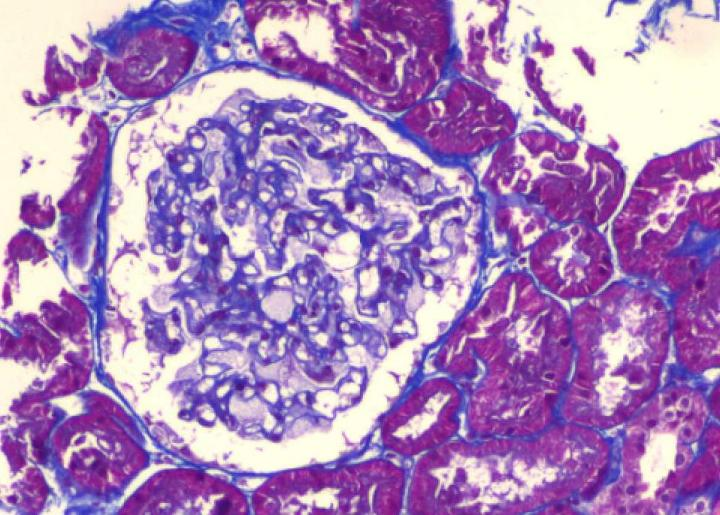

肾小管上皮细胞空泡变性,可见少量蛋白管型,灶状萎缩(萎缩面积约15%);

肾间质灶状单个核细胞浸润,小动脉大致正常,细动脉节段性玻璃样变;

Masson×200 肾小球上皮细胞肿胀伴空泡变性、泡沫细胞形成

光镜:肾小球上皮细胞肿胀伴空泡变性、泡沫细胞形成(神经鞘脂沉积);甲苯胺蓝染色可见嗜甲苯胺蓝颗粒在足细胞、小管上皮细胞以及壁层上皮细胞多部位沉积。